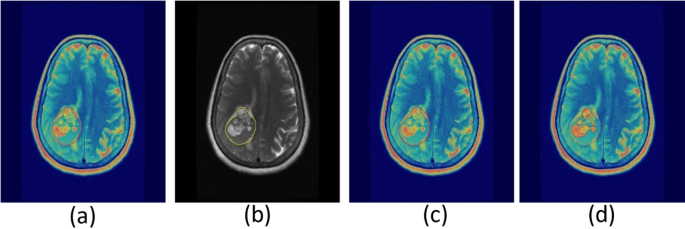

To enhance the precision of tumor delineation in PET/MRI imaging, it is essential to refine the imaging process by excluding structures such as the skull bone and meninges. As shown in Fig. 2, this refinement involves copying the PET delineation onto the MRI image to define initial boundaries (Fig. 2a and b). Subsequently, the MRI is employed to exclude the skull bone and meninges from the region of interest (ROI) (Fig. 2c). The delineation is further enhanced using adaptive thresholding techniques (Fig. 2d). These refinements are critical for achieving accurate boundary definitions and improving diagnostic precision.

These noteworthy findings not only contribute valuable insights to the existing body of knowledge pertaining to PET imaging data and tumor volume estimation through image segmentation but also hold substantial promise in informing and shaping future endeavors within this domain. Segmentation accuracy plays a critical role in the precise delineation of tumor boundaries in imaging studies. As demonstrated in Fig. 5, a transaxial slice comparison highlights the difference between traditional and adaptive thresholding methods. The adaptive approach shows improved accuracy in defining tumor regions, underscoring its potential for enhancing imaging precision and clinical decision-making.